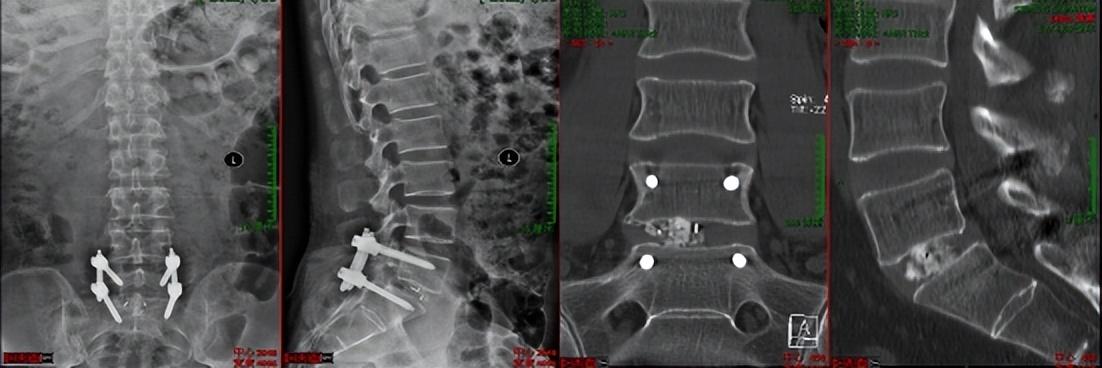

第二例病例为腰椎峡部裂患者。为其实施了VBE下的经椎间孔椎间融合术(TLIF)。患者术前腰痛伴右大腿后方疼痛1年余。术后第二天可下床活动,腰腿痛缓解。

术中操作

术后复查及患者情况

患者术后第二天可佩戴腰围下床活动